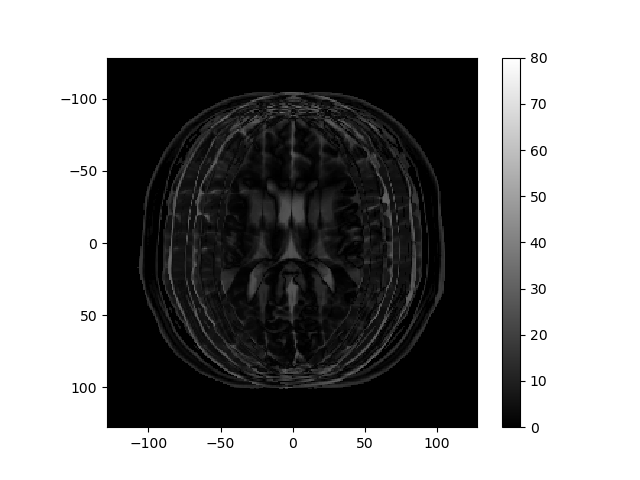

The left image below shows the magnitude of the k-space data obtained for an MRI, and the right image shows the reconstructed image.

Consider how the image would change if the k-space data were multiplied by \sin^2(\cdot) or \cos^2(\cdot) of k_r or k_c. Below are several k-space representations that have been distorted in this way. In each case, assume that only the magnitude of the k-space data is changed. Match each k-space image with the corresponding reconstructed image, and enter your results from the corresponding pull-down list.